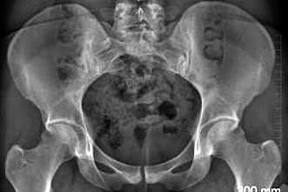

In the normal hip, the acetabular opening is anterior. In the retroverted condition, the superior aspect of the acetabulum is tilted posteriorly. On the AP X-ray in a normal acetabulum, the anterior rim of acetabulum should always project medial to the posterior wall. In cranial acetabular retroversion, the anterior rim will project lateral to the posterior wall in the superior aspect of the acetabulum.

Figure 1: Edge of anterior acetabular wall (yellow line) is medial to the edge of posterior wall (red line), even in superior aspect of acetabulum. Note that these lines never cross. Green line is rim of the pelvis, iliopectineal line. Blue line is acetabular teardrop.